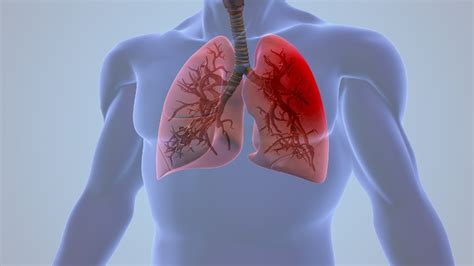

Pneumoniją nuo peršalimo skiria simptomų lokalizacija ir sunkumas. Jei peršalimas yra „galvos” liga (sloga, gerklė), tai pneumonija yra „krūtinės” liga. Esminis skirtumas - kvėpavimo sunkumai. Sergant peršalimu, dusulio nebūna (nebent nosis visiškai užgulta). Sergant pneumonija, jaučiamas oro trūkumas ateina iš plaučių gilumos.

Atipinis plaučių uždegimas - kai ligonis neturi ne tik aukštos temperatūros, bet ir kitų įprastų požymių, kuriuos dažniausiai siejame su pneumonija (plaučių uždegimu). Besimptomis plaučių uždegimas - tai ligos forma, kai nepasireiškia tipiški simptomai, tokie kaip karščiavimas, kosulys ar krūtinės skausmas. Vietoje to pasireiškia tik bendresni negalavimai: nuolatinis silpnumas, energijos stoka, miego sutrikimai, naktinis prakaitavimas, sumažėjęs apetitas ar dusulys net atliekant kasdienius darbus. Toks netipiškas pasireiškimas ypač dažnas kūdikiams, vyresnio amžiaus žmonėms ar pacientams, kurių imunitetas nusilpęs. Besimptomis plaučių uždegimas neretai nustatomas pavėluotai arba atsitiktinai, kadangi liga progresuoja tyliai ir dėl tokių „užmaskuotų“ simptomų pacientai laiku nesikreipia į gydytoją. Būtent vėlyva diagnozė kelia didžiausią pavojų, nes laiku nepradėjus gydymo ši ligos forma gali komplikuotis į kvėpavimo nepakankamumą, pleuritą (plaučių gleivinės uždegimą) ar infekcijos išplitimą organizme. Egzistuoja ir klastinga ligos forma, vadinama atipine arba „vaikščiojančia” pneumonija (angl. walking pneumonia). Ją dažniausiai sukelia Mycoplasma pneumoniae bakterijos.